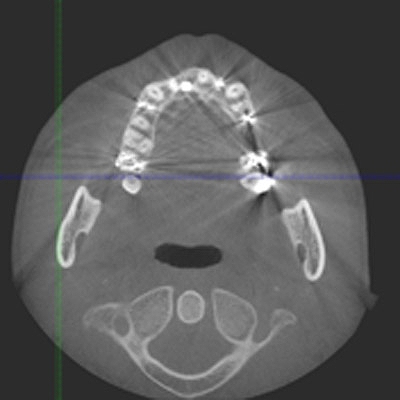

CTにより解剖学的形態を避け、安全に顎骨内にインプラントを埋入することが大切です。 CTが無いとインプラントはリスクが高いです

CTにより解剖学的形態を避け、安全に顎骨内にインプラントを埋入することが大切です。 CTが無いとインプラントはリスクが高いです

歯が割れているのですが、、、

口蓋側寄りに埋入しています

頬側は骨造成をしています頬側は

頬側は骨が3mm以上ないといけません